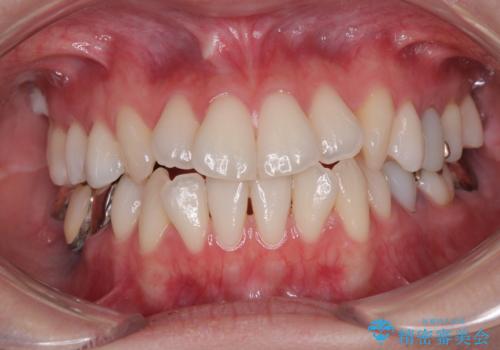

【モニター】前歯のデコボコをインビザラインで綺麗に

- 上下前歯のデコボコとクロスバイトを気にして来院された患者様です。

治療済みの処置歯が多いため、インビザラインを用いて矯正治療を行うこととしました。

下顎臼歯部にブリッジが装着されており、移動不可のため、IPR(歯と歯の間を削る)と歯列全体を拡大させることで、歯並びを整えていくこととしました。

インビザライン特有の奥歯の噛みにくさが治療後半に発現しましたが、無事に終了させることができました。